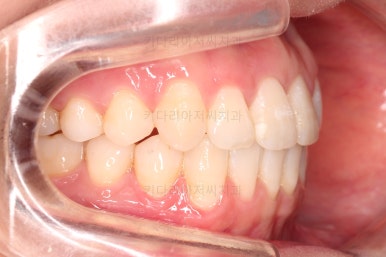

이번 환자분이 선택하신 장치는 데이몬 클리어라고 하는 자가결찰 세라믹 장치인데요.

데이몬 클리어는 현재 사용되는 세라믹 장치 중에 가장 심미성이 뛰어난 장치입니다.

흔히 세라믹 장치로 많이 아시는 클리피씨, 엠파워 클리어 등을 철사를 잡아주는 캡이 메탈로 되어 있어 유심히 관찰하면 메탈 부분이 있는 반면에 데이몬 클리어는 캡 자체도 세라믹으로 되어있어 심미성이 좋습니다.

다만, 통 바디 형태의 세라믹으로 되어있다 보니 강도 증가를 위해서 부피가 약간 더 커진 단점은 있습니다.

상하좌우 총 4개의 미니스크류를 이용해서 치열을 뒤로 당겨줍니다.

중간평가를 하면서 환자분과 가능한 수준/원하는 수준을 잘 조율해 가면서 입매를 정해갑니다.